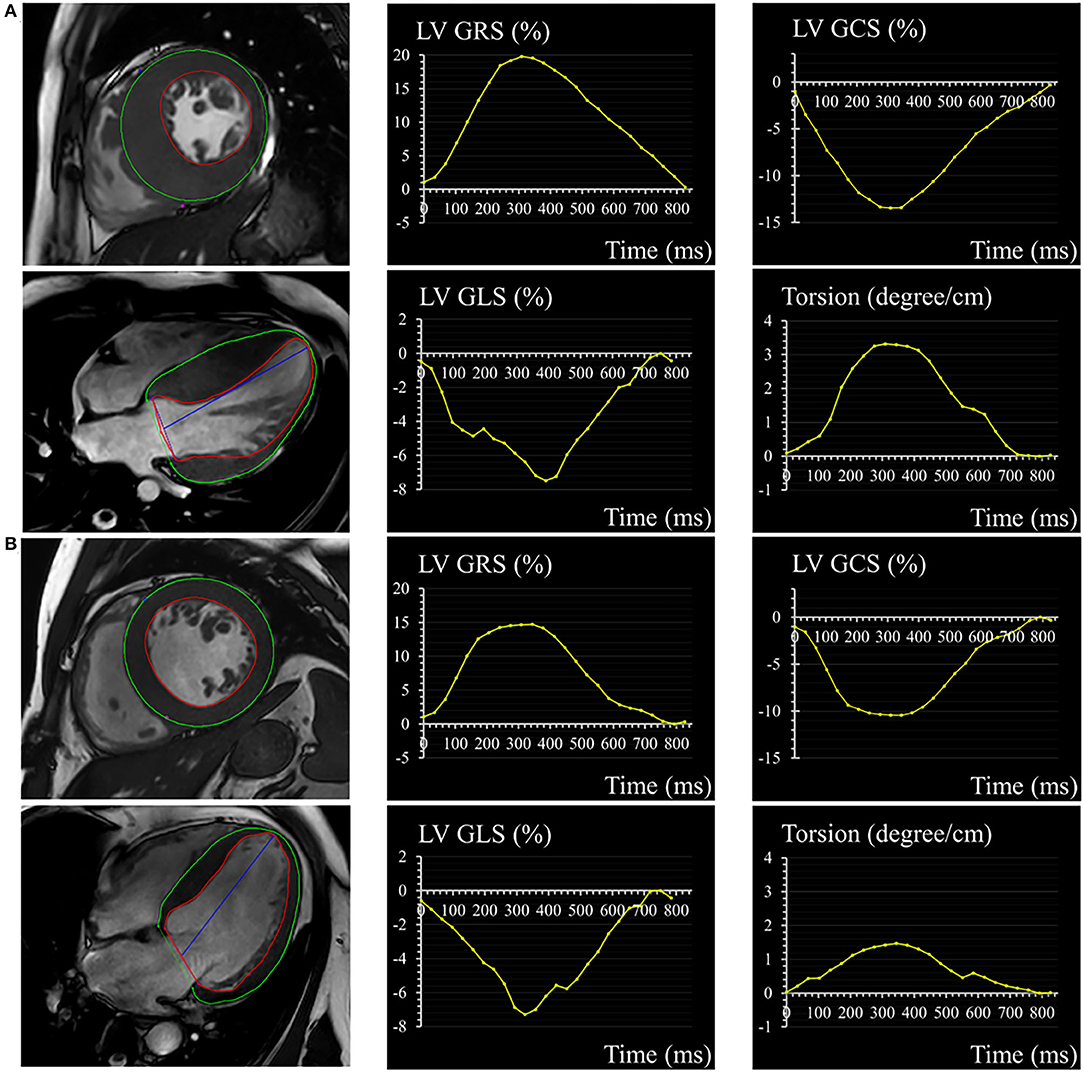

Cardiovascular magnetic resonance feature tracking-derived strain and strain rate were used to evaluate myocardial deformation. Quantitative parameters included radial, circumferential, and longitudinal orientation (Figure 1). Radial strain and circumferential strain were calculated from two-dimensional short-axis planes and longitudinal strain was derived from two-dimensional long-axis plane. Regional strain analysis was also performed by dividing left ventricular into basal, mid, and apical segments by 2-dimension. Strain rate was measured as a derivative of the strain tensor and it represented the rate of deformation (15). The LV torsion was calculated as the ratio of the peak difference of ventricular apical and basal rotation at the same time point in the cardiac cycle to the distance between their short-axis slices (13).

Figure 1. A 32-year-old male with HCM (A) and a 56-year-old male with HHD (B). Epicardial (green) and endocardial (red) contours, as well as the corresponding curves of LV GRS, GCS, GLS, and torsion in HCM and HHD. HCM, hypertrophic cardiomyopathy; HHD, hypertensive heart disease; LV, left ventricular; GRS, global radial strain; GCS, global circumferential strain; GLS, global longitudinal strain.